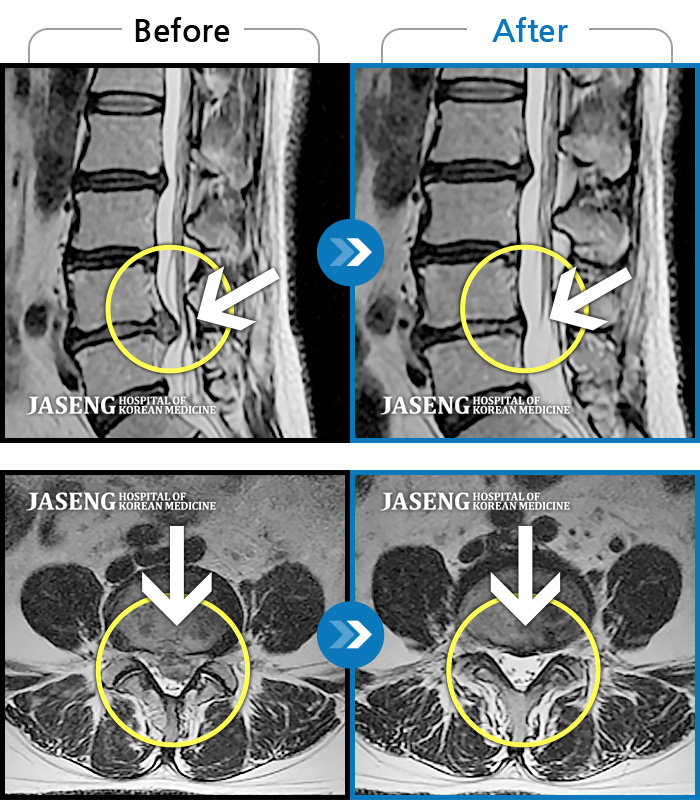

휴직중 허리디스크로 걷지도 못하고 정형외과에서 전부 수술을 권유하는 저에게 비수술로 희망을 주셨어요~^^

지금도 통증이 있으면 통원을 가는데 갈때마다 한결 같으신 원장님 추천합니다~^^